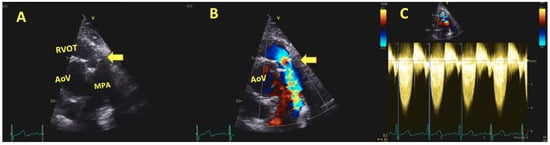

6.3. Post-Operative and Long-Term Follow-Up Imaging